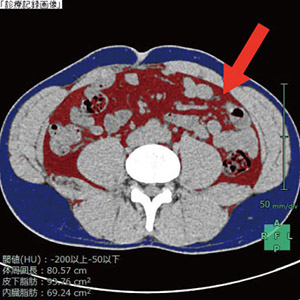

<内臓脂肪CT結果画像>

CT結果画像の赤い部分が内臓脂肪です!!!

内臓脂肪面積はCTを使って測定します。やはり腹囲の測定のみでは、正確に内臓脂肪の量を測定することはできません。同時に皮下脂肪も測定するので、太っているけれど内臓脂肪型肥満ではないということもわかるかもしれません。(もちろんその逆もあります。)

『肥満』のなかでも内臓脂肪面積が100㎠以上の場合は、脳梗塞や心筋梗塞などの危険度がより増すため『内臓脂肪型肥満』と呼ばれます。